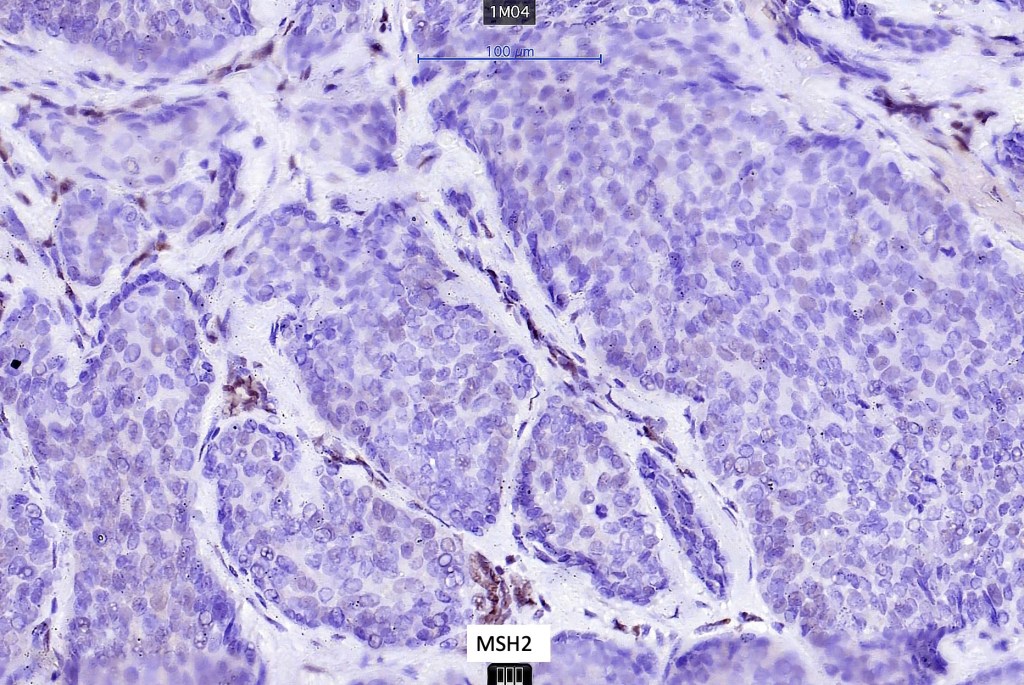

Sebaceous carcinoma from a patient with Muir-Torre syndrome kindly shared by Dr. Antonina Kalmykova.

Immunohistochemistry (from the Muir-Torre patient except for EMA which was shared by Dr. Tsheri Dorji